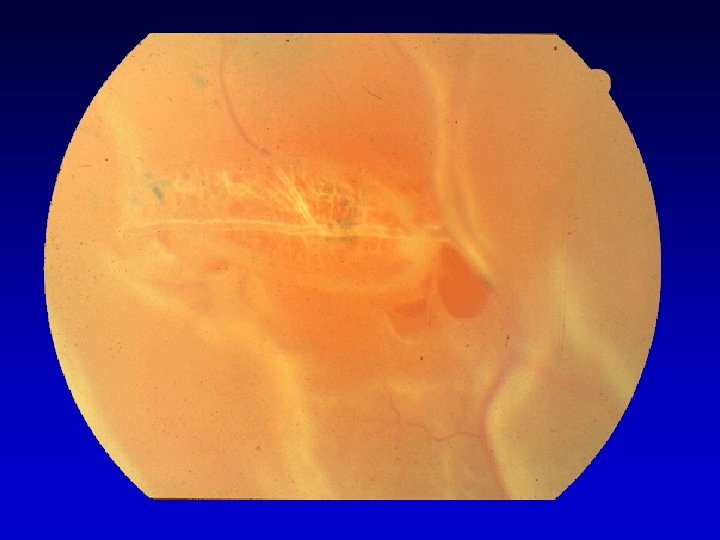

AREA DI DEGENERAZIONE ASSOTTIGLIAMENTO Condizione necessaria ma non sufficiente SOLUZIONE DI CONTINUO A TUTTO SPESSORE ( foro, lembo ) DISTACCO DI RETINA

Degenerazioni retiniche regmatogene Insieme di lesioni polimorfe della retina periferica, della corioretina e del vitreo con aspetto clinico e istopatologico differente.

Byer divide in: CLINICAMENTE INSIGNIFICANTI Varianti normali - complessi e pieghe meridionali - baie orali incluse CLINICAMENTE REGMATOGENE Degenerazione a lattice Formazioni granulari cistiche (tuft) Varianti anomale - ciuffi di trazione zonulare Degenerazioni periferiche varie - degenerazione cistoide - degenerazione pavimentosa - cisti pars plana - perle ora serrata - bianco con pressione Retinoschisi degenerativa Rotture retiniche